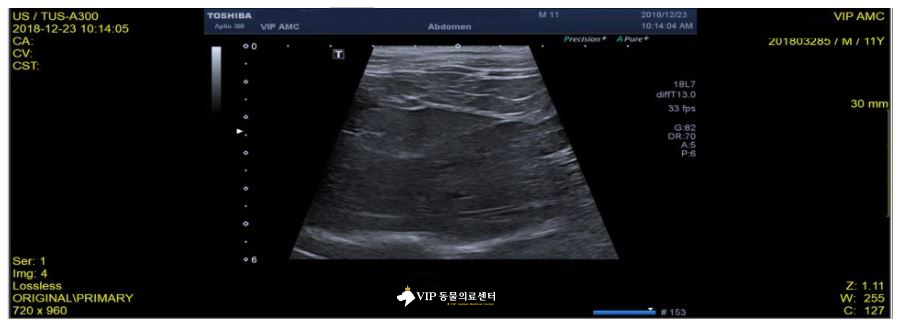

고양이 용식이의 초음파 검사 상에서는 간 크기 증가, 간 에코의 전반적인 상승이 확인되었습니다. 췌장, 담낭 등은 특이사항없이 양호하였습니다.